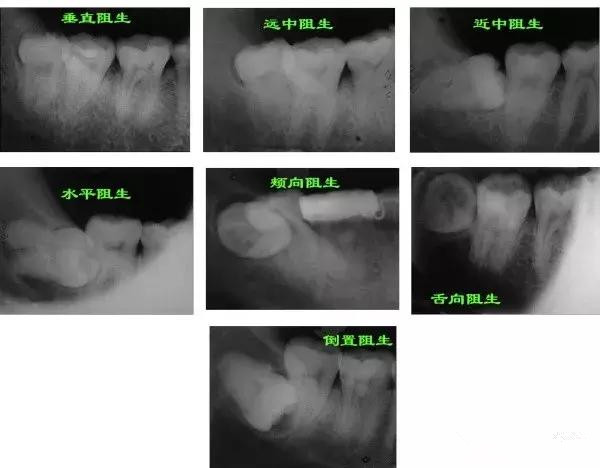

总结来说,下颌智齿有七种方法让你跪下叫爸爸(点开原图放大,对号入座):

七种最常见的是近中阻生和水平阻生

最极品的就是倒置阻生了